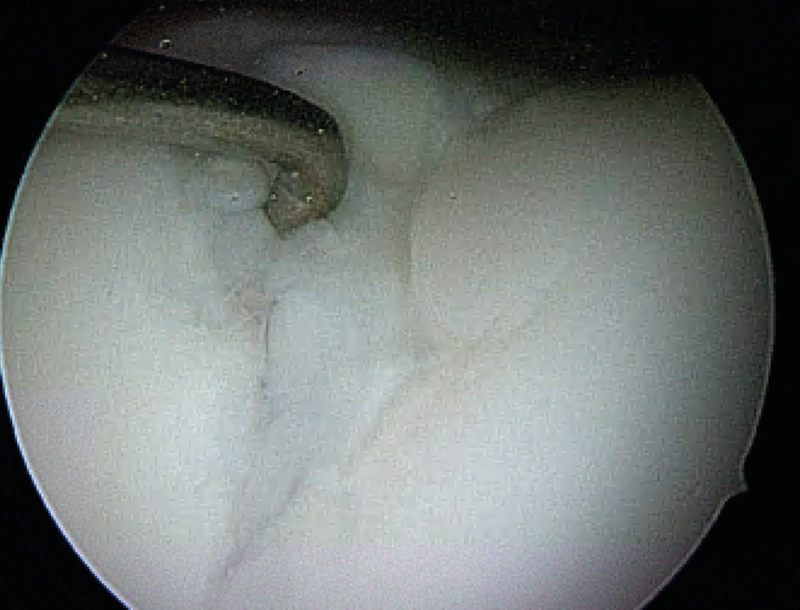

Microfracture surgery (Mfx)

It can be performed quickly, without complications, cheap and with surgery instruments that are available at any time (Fig. 11).

In practice, care must be taken to clean up the subchondral calcifying layer without grossly damaging the subchondral lamella (Fig. 12).

If possible, the use of finer grade reamers called “nano fracturing”, (Fig. 13) or low-speed microdrilling (Fig. 14) with K-wires (1.0−1.6 mm) should be favoured.

The common larger chondro picks tend to result in confluent fine subchondral fractures and increase the risk of intralesional osteophyte formation (Fig. 15) and subchondral cyst formation.